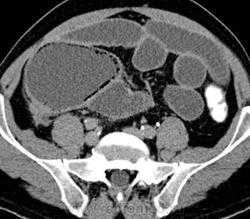

Данные, полученные при КТ, помогают сузить дифференциально-диагностический ряд состояний, приводящих к утолщению стенки желудка. Так же, как в тонкой и ободочной кишке, воспалительный процесс (гастрит) приводит к отеку подслизистой основы, которая выглядит как гиподенсная полоска с плотностью, близкой к плотности воды, расположенная между слизистой и серозной оболочками. Компонент мягкотканной плотности в стенке больше характерен для неопластического процесса. КТ также позволяет отличить друг от друга различные опухоли желудка.

Первичный рак обычно обусловливает утолщение стенки в виде узла с неправильными контурами, ограничение растяжимости стенки, часто в сочетании с признаками вторичного поражения печени, регионарных лимфоузлов и, в некоторых случаях, сальника.

При лимфоме желудка часто наблюдается в значительной степени выраженное утолщение складок слизистой оболочки узлового характера, но нетипично снижение способности желудка к растяжению или возникновение обструкции. При лимфоме и метастазах в желудок часто выявляются вторичные очаги иной локализации.

При КТ часто можно выявить другие причины утолщения складок слизистой оболочки желудка: панкреатит, признаки островковоклеточной опухоли поджелудочной железы при синдроме Золлингера-Эллисона, проявления цирроза печени и портальной гипертензии у пациента с варикозным расширением вен желудка.